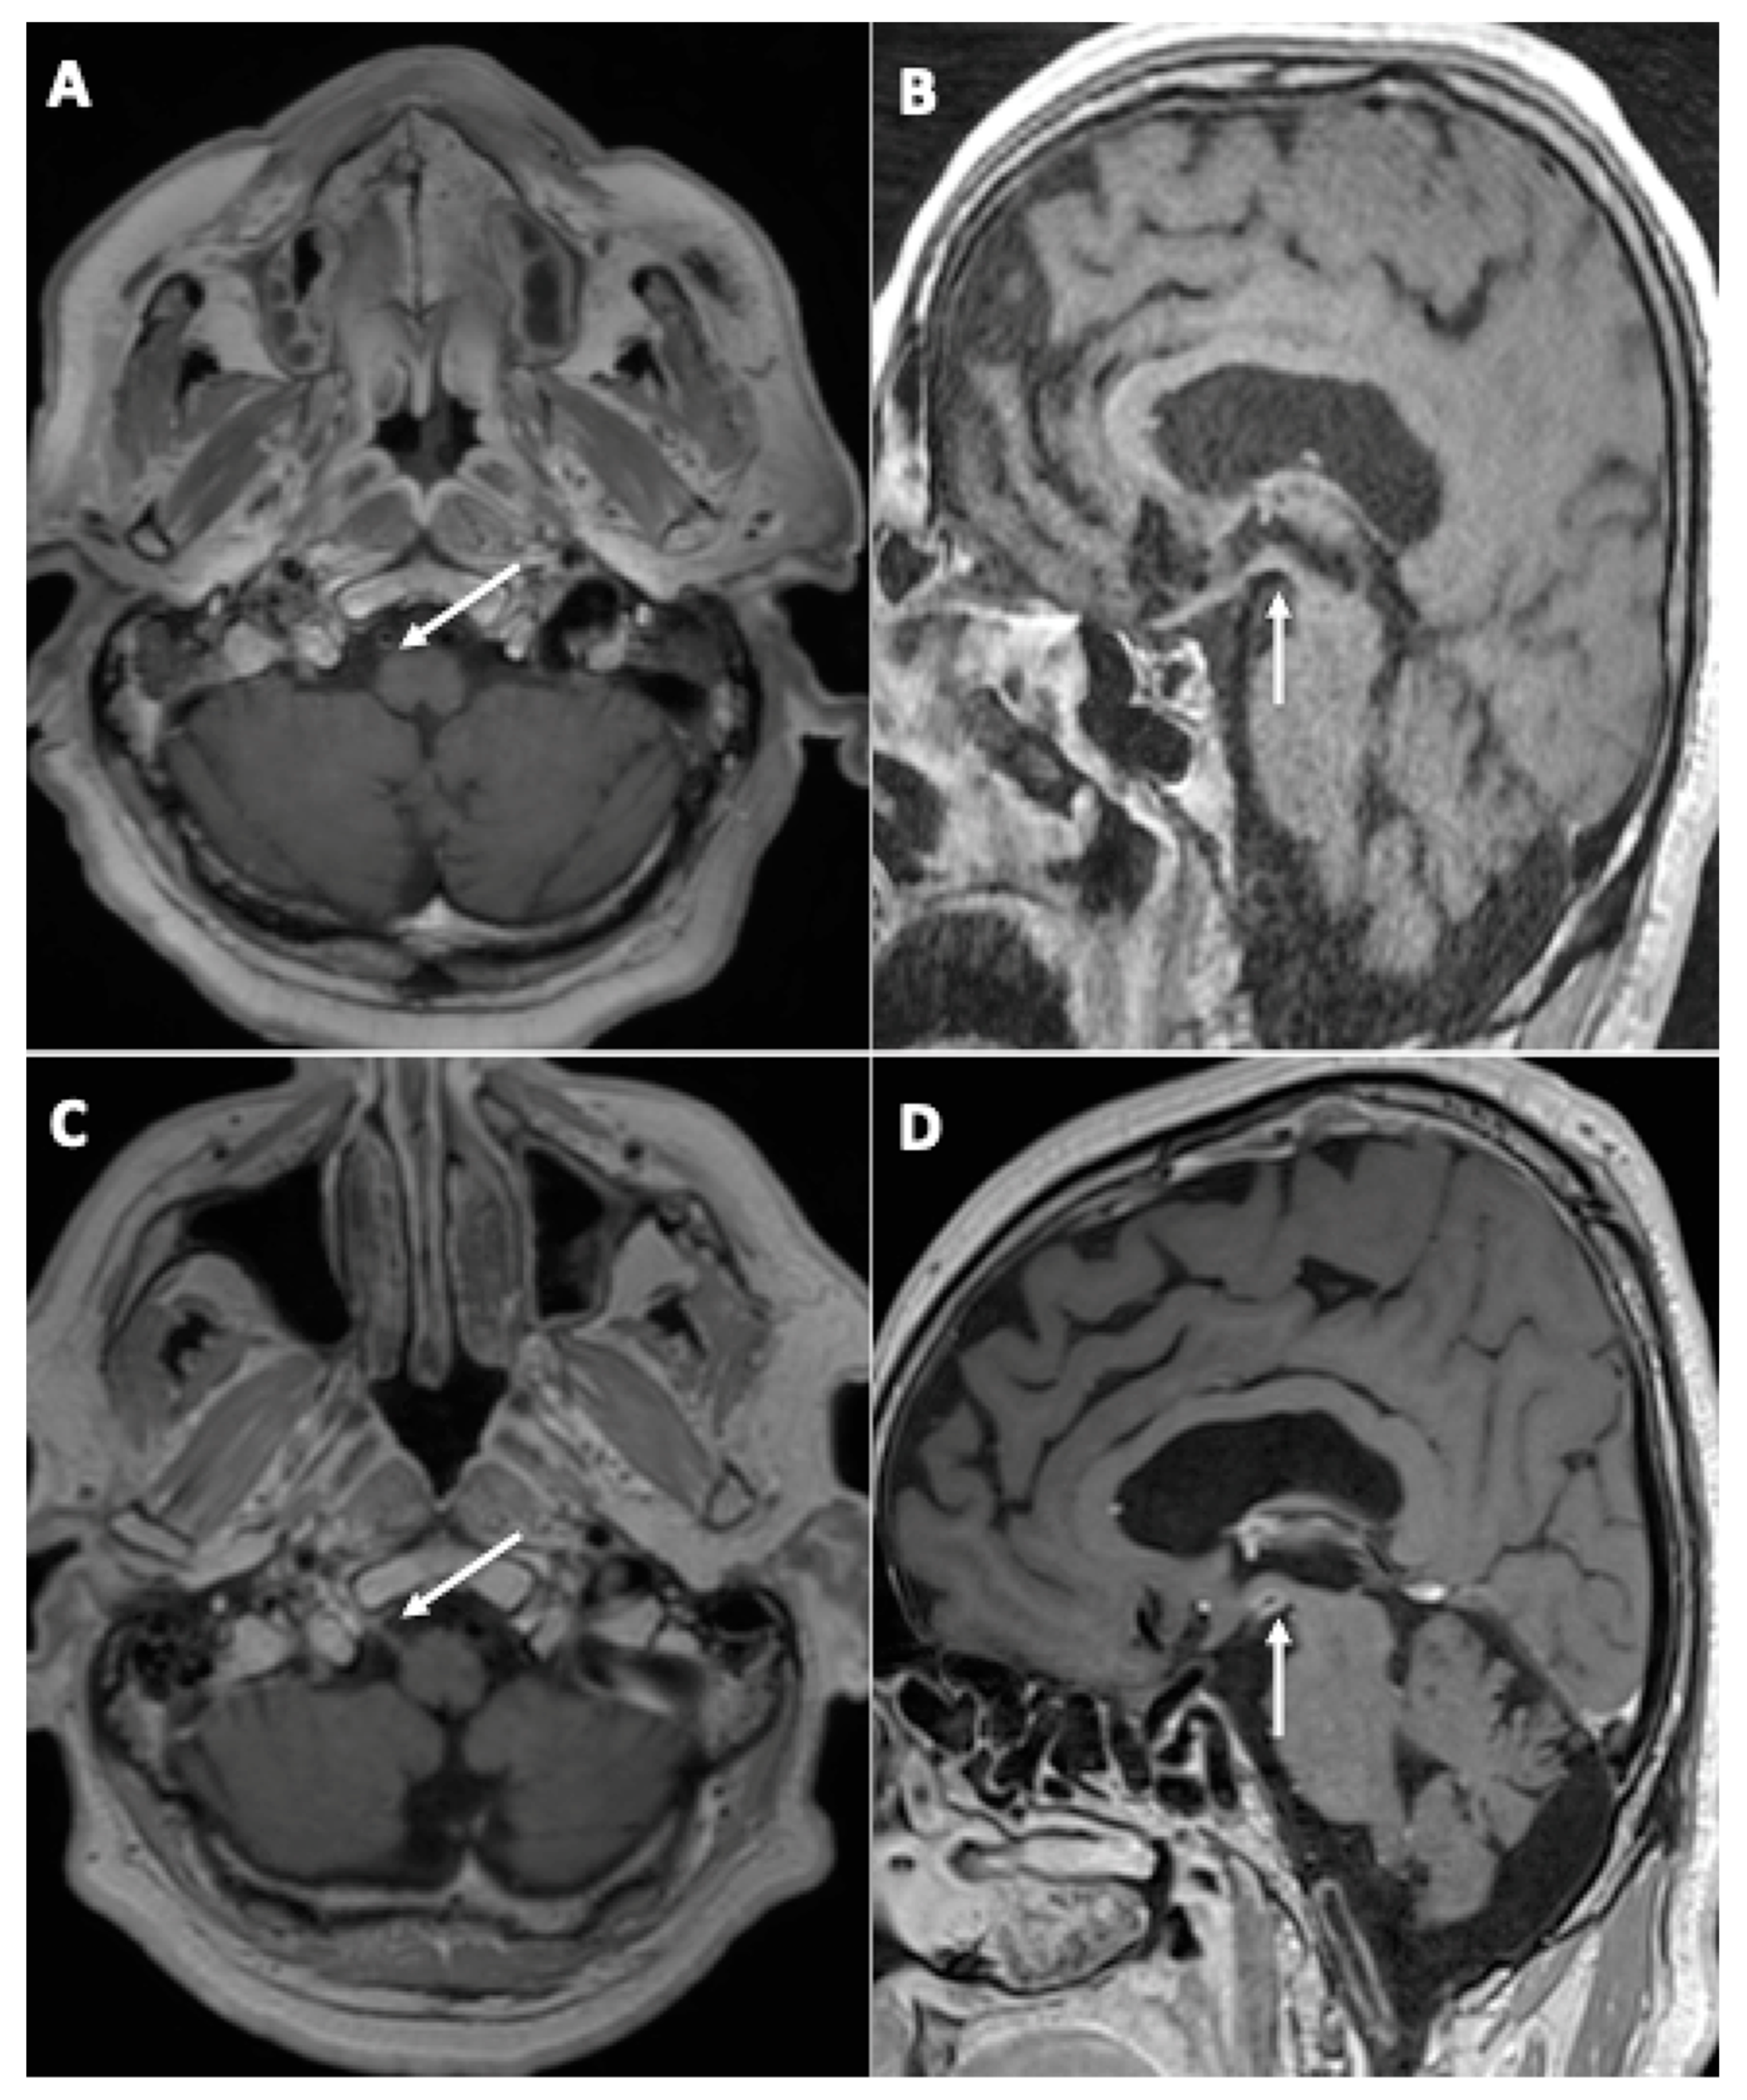

3.1. Brain MRI Findings

- Initial brain MRI findings

- Fourteen (45%) cases of focal (single focus or multiple foci) leptomeningeal enhancement (LME);

- Nine (29%) diffuse brain microhemorrhages, which predominantly involved the corpus callosum, the subtentorial juxtacortical WM, the internal capsule, the brainstem, the middle cerebellar peduncles, and the cerebellum, leading to the diagnosis of critical-illness associated cerebral microbleeds (CIAM) [14];

- Four (13%) acute ischemic strokes (acute small vessel infarcts or borderline infarction);

- Evolution of initial neuroimaging findings

- New findings during follow-up

- Evolution of perfusion imaging

- Chammas, A.; Namer, I.J.; Lersy, F.; Kremer, S.; Bund, C. Inferior Colliculus’s Hypermetabolism. Clin. Nucl. Med. 2021, 46, 413–414. [Google Scholar] [CrossRef] [PubMed]

- Chammas, A.; Bund, C.; Lersy, F.; Brisset, J.-C.; Ardellier, F.-D.; Kremer, S.; Namer, I. Collicular Hyperactivation in Patients with COVID-19: A New Finding on Brain MRI and PET/CT. Am. J. Neuroradiol. 2021, 42, 1410–1414. [Google Scholar] [CrossRef] [PubMed]